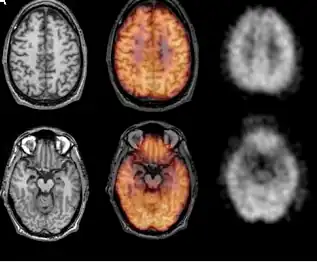

Diagnosis

Definitive diagnosis of FTDP-17 requires a combination of characteristic clinical and pathological features and molecular genetic analysis. Genetic counseling should be offered to affected and at-risk individuals; for most subtypes, penetrance is incomplete.